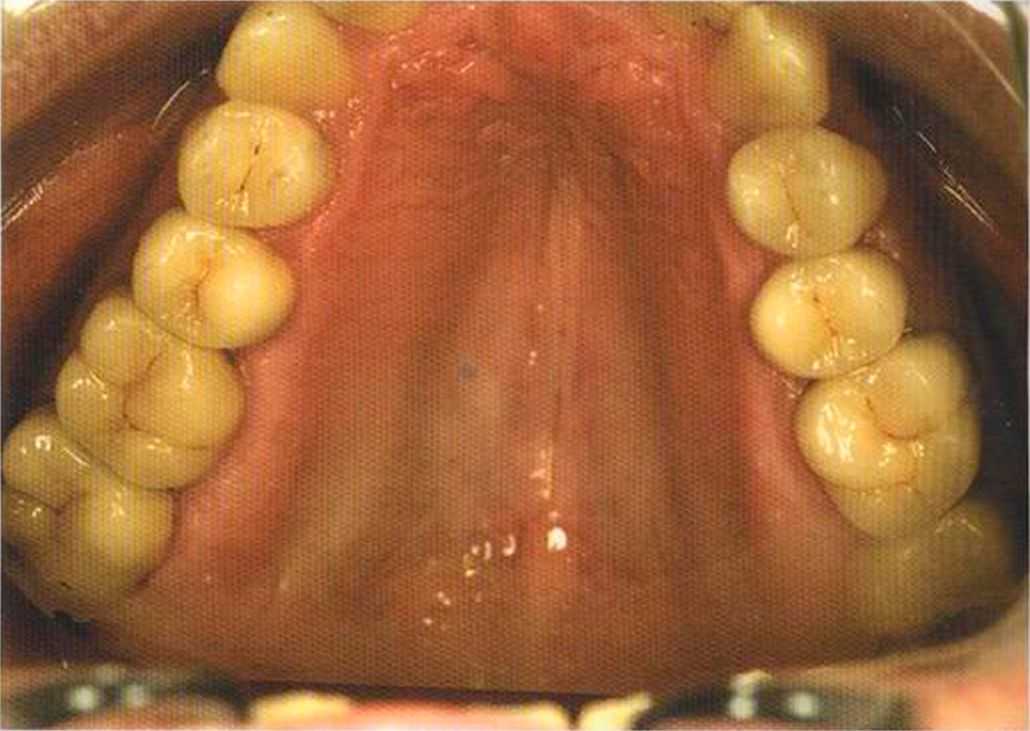

Только что зацементированная работа в полости рта. Цементирование керамических вкладок осуществлено на цемент двойного отверждения Vivadent, а коронок ln-Сегат на Panavia ТС.

Здесь были установлены керамические, послойно нанесенные вкладки. Они выглядят более живыми по сравнению с прессованными.